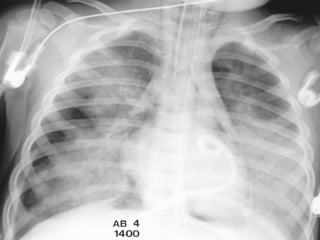

Notice the increased lucency of the cardiophrenic sulci in this patient

with inferior anteromedial pneumothoraces. A CT scan confirms the

diagnosis

 a hyperlucent upper

quadrant with

visualization of the

superior surface of the

diaphragm and

inferiorvena cava.

 double-diaphragm

sign

 Antero lateral air may

increase the

radiolucency at the

costo phrenicsulcus.

This is called the deep

sulcus sign.